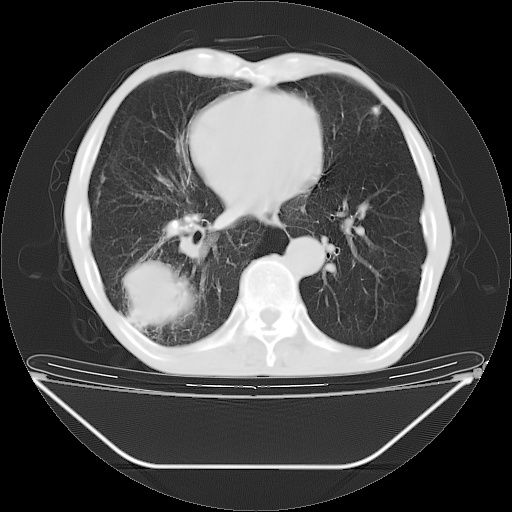

以下是引用随光逐影在2008-8-25 22:03:00的发言:[br]1)考虑右肺下叶周围性肺癌并肺内转移,腰椎附件转移。2)左上肺结核(结核球形成)。3)双肺肺气肿(多发肺大泡形成)。4)双肺门区及纵隔内多发淋巴结钙化。

以下是引用zsl6918在2008-8-25 21:55:00的发言:[br]符合右肺周围性肺癌并肺内转移,左肺结核球。双肺肺气肿。腰椎附件转移。

以下是引用qc80012345在2008-8-26 6:14:00的发言:[br]符合右肺周围性肺癌并肺内转移,左肺结核球。双肺肺气肿。腰椎附件转移。